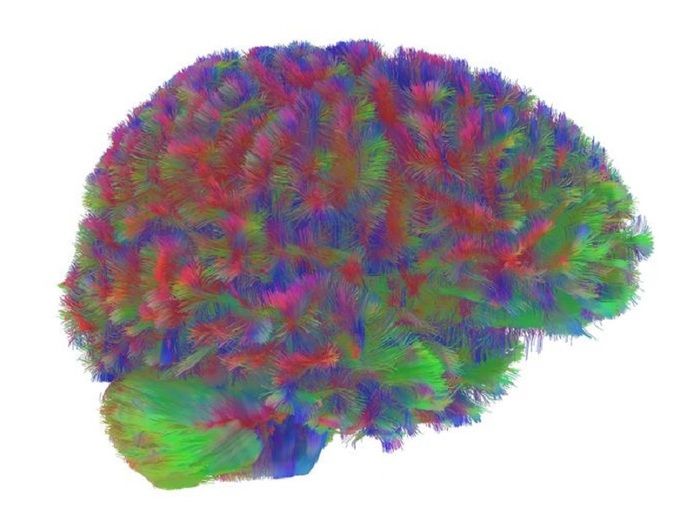

Come tutti gli altri organi, seppur in forme e modi diversi, anche il cervello è dinamico e le connessioni che si strutturano tra i neuroni cambiano nel tempo. Trasformazioni che i ricercatori britannici hanno analizzato usando scansioni di Risonanza magnetica, grazie alle quali è stato possibile mappare le varie connessioni neurali, fatte su 3.802 persone di età compresa tra zero e novant'anni .